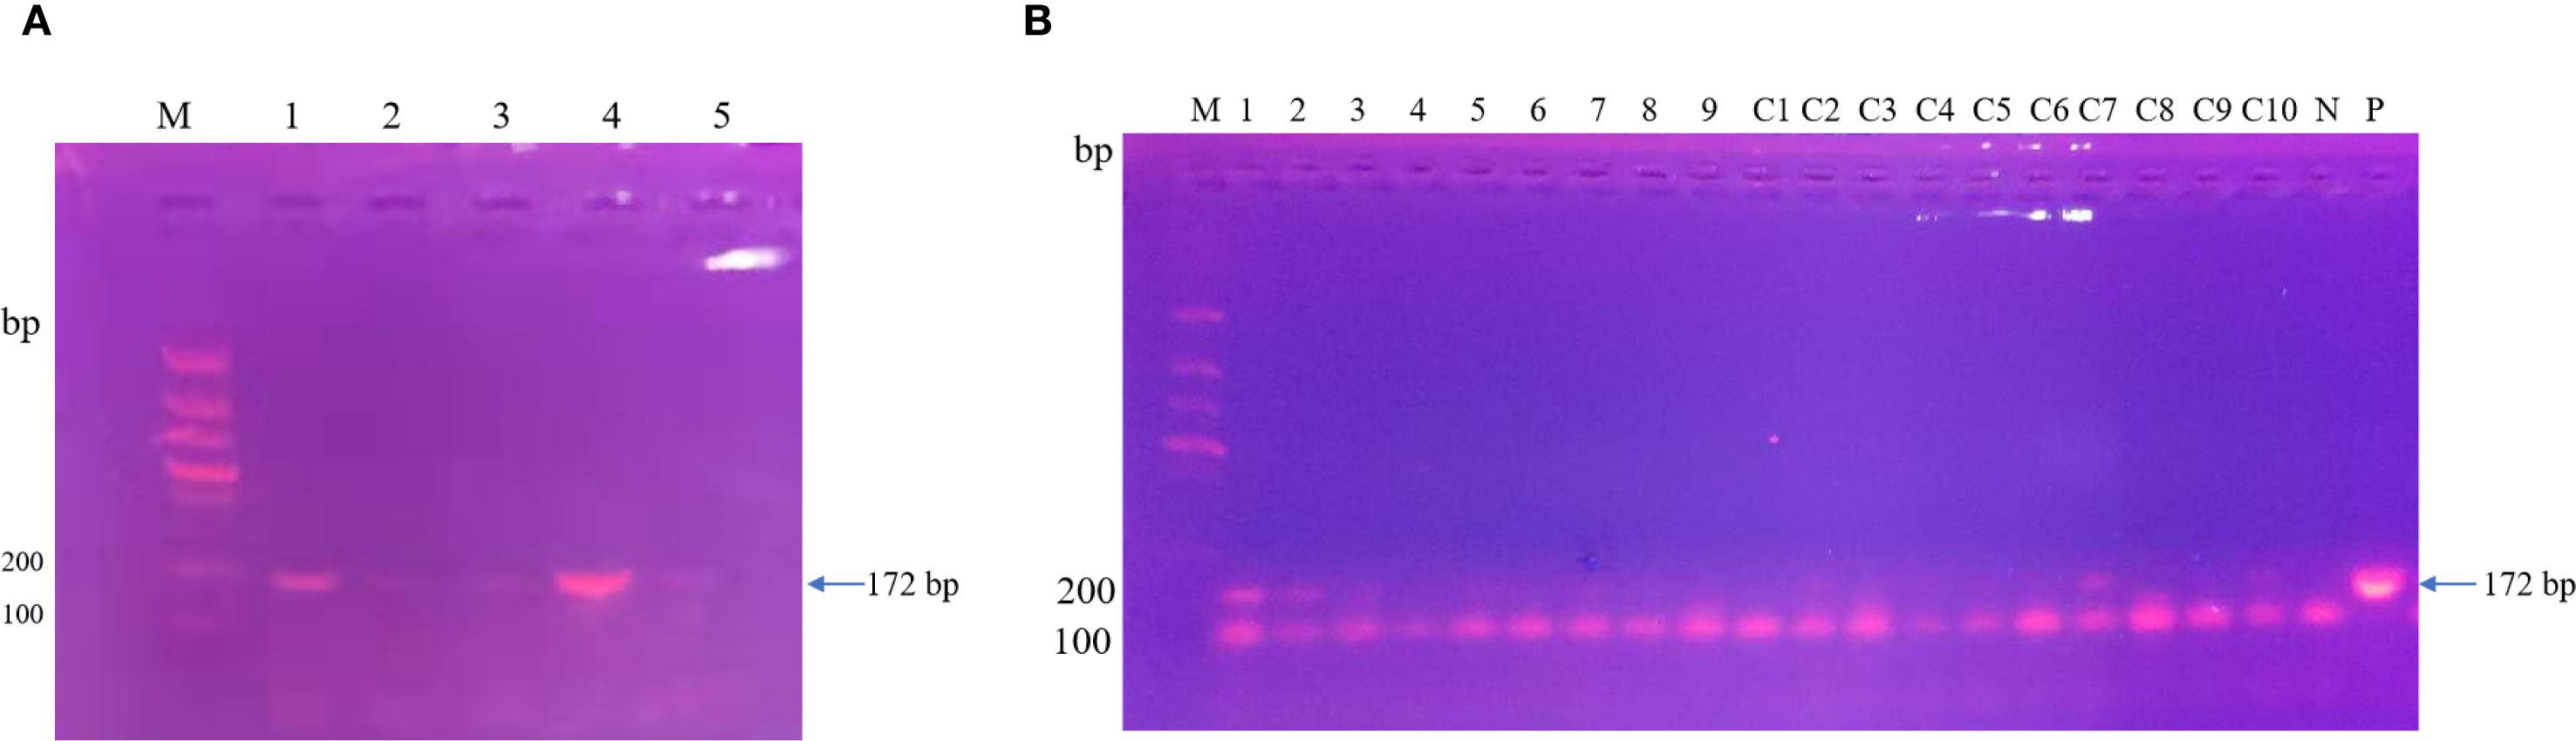

After the patient’s hospital admission, his chest X-ray revealed bilateral pneumonia and ground-glass opacity, and he was prescribed oxygen therapy and doxycycline. Afterward, lesions with ground-glass opacity were reduced, but pulmonary consolidation was still observed in the lungs (Supplementary Figure S2). Based on 23S rDNA amplification, a positive 172-bp band of C. psittaci was detected in the patient’s alveolar wash, while his tracheal mucosa and throat swabs were negative (Figure 1A). Other family members, the nurses, the attending physician, and the house chickens were negative for C. psittaci (Figure 1B). Afterward, qPCR results showed that the patient’s alveolar wash was positive for C. psittaci. Subsequently, positive C. psittaci was identified in the patient’s alveolar wash and throat swab, and his sons’ throat swab. However, a negative reaction was found in his tracheal mucosa and other close contacts’ samples (Figure 2). The ompA gene sequence of the C. psittaci strain was determined and submitted to GenBank (accession number: OR616243). After inoculation into SPF embryonated eggs, typical intracellular inclusions were observed using immunofluorescence staining (Figure 3).

Figure 1. Detection of Chlamydia psittaci from patient’s samples and his close contacts using 23S rDNA PCR. (A) Positive C. psittaci was detected in the patient’s alveolar lavage (M, marker; 1, alveolar lavage; 2, throat swabs; 3, tracheal mucosa; 4, C. psittaci 6BC control; 5, negative control). (B) Negative samples of patient’s close contacts (M, marker; 1–7, patient’s relatives; 8, doctor; 9, nurse; C1–C10, chicken samples; N, negative control; P, positive control).